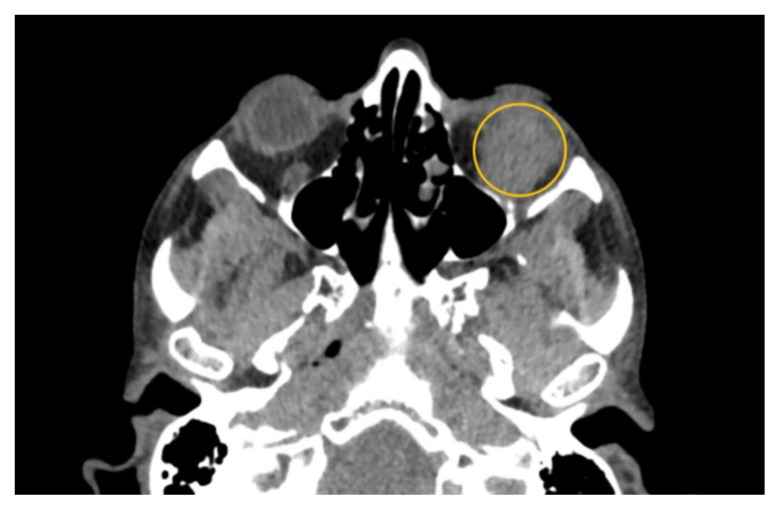

软组织感染,包括脓肿,是急诊科经常遇到的。然而,下直肌脓肿是罕见的,可能会提出独特的诊断和治疗挑战,由于缺乏文献病例。本病例报告强调了一名47岁男性,因急性耐甲氧西林金黄色葡萄球菌感染而出现左下直肌脓肿的治疗。影像显示明显的积液压迫左眼球,引起眼球运动受限和其他症状。尽管先前静脉注射抗生素,脓肿仍然存在。虽然静脉注射抗生素是治疗的重要组成部分,但本病例强调了单独使用这种方法的潜在不足,强调需要手术干预,如眼窝切开引流。本报告补充了关于下直肌脓肿的有限文献,并强调了进一步研究和临床关注以优化患者预后的必要性。主题:脓肿、软组织感染、眼外肌、化脓炎、耐甲氧西林金黄色葡萄球菌、眼球突出、复视、视力丧失。

Soft tissue infections, including abscesses, are frequently encountered in the emergency department. However, abscesses of the inferior rectus muscle are rare and may present unique diagnostic and therapeutic challenges due to the scarcity of documented cases. This case report highlights the treatment of a 47-year-old male presenting with an abscess in the left inferior rectus muscle due to an acute Methicillin-resistant Staphylococcus aureus infection. Imaging revealed a distinct fluid collection compressing the left globe, causing restricted ocular motility and other symptoms. Despite prior intravenous antibiotics, the abscess persisted. While intravenous antibiotics are an important component of treatment, this case highlights the potential insufficiency of this approach alone, emphasizing a need for surgical intervention such as orbitotomy for drainage. This report contributes to the limited literature on inferior rectus muscle abscesses and underscores the need for further research and clinical attention to optimize patient outcomes.